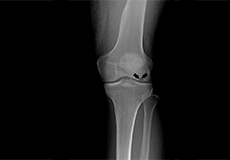

Pseudogout

Pseudogout is a type of arthritis that is characterized by the development of a painful swelling that occurs suddenly in one or more joints. It is also known as calcium pyrophosphate deposition disease (CPPD) because of the type of crystals that are deposited on the joint during the disease process.